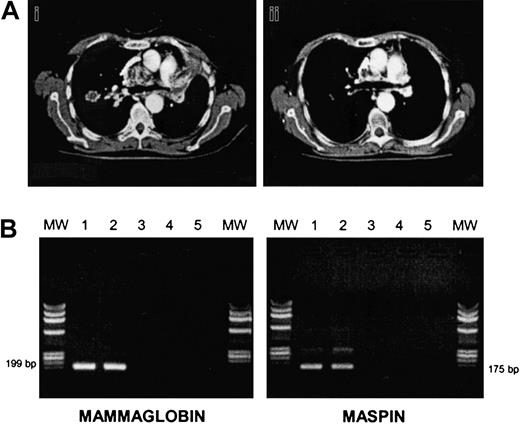

There were 3 of 7 RCC patients who progressed soon after the transplantation (median time, 61 days). There were 4 patients who responded after CSA withdrawal; patient no. 7 relapsed but eventually responded again to DLIs plus IFNα (Figure1A). The other 2 RCC patients had stable disease, and patient no. 11 (papillary RCC) died of progressive disease 10 days after the first DLI. In all BC patients, disease progressed at a median of 69 days after the transplantation (range, 41-232 days). In order to induce a GVT effect, all patients (except patient no. 5 who died of progressive disease at day +109) received escalating doses of DLIs, at a median of 51 days after disease progression (range, 12-78). We observed 2 partial responses (patients no. 3 and no. 6): one after a single-dose DLI, the other after 2 infusions followed by IFNα. Patient no. 3 had an extensive skin and lymph node involvement before allografting that partially regressed along with a grade II acute GVHD developing after DLI. Patient no. 6 was unique since she had bone marrow involved by disease before and after allografting, and bone lytic metastases. BC cells were still present in the marrow before DLI, as assessed by morphology, cytokeratine immunohistochemistry, and by RT-PCR for maspin and mammaglobin genes. After DLI plus IFNα she developed a grade II acute GVHD, and then marrow samples became PCR-negative for maspin and mammaglobin gene expression (Figure 1B). We and others have previously shown that RT-PCR for maspin and mammaglobin is a sensitive and specific assay for detecting occult BC cells.13 This finding suggests a GVT effect at the marrow level.

Responses to allografting in renal cell cancer and breast cancer.

(A) CT thorax scan of patient no. 7 before (i) and after (ii) DLI plus IFNα. (B) RT-PCR analysis of mammaglobin and maspin expression in bone marrow cells of patient no. 6 before and after DLI. Bone marrow mononuclear cells were analyzed for mammaglobin and maspin expression preallograft (lane 1), before DLI (lane 2), and after DLI (lane 3), respectively. Lane 4: negative control; lane 5: no DNA. MW indicates molecular weight marker.